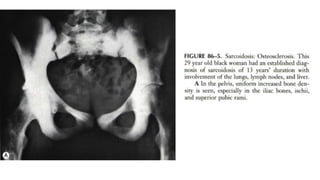

 Other skeletal areas that may be affected by sarcoidosis include nasal

bones, pelvic girdle structures, ribs, and the skull.

 Other skeletalareas that may be affected by sarcoidosis include nasal bones, pelvic girdle structures, ribs, and the skull.  Lesions in the pelvic bones or in the spine may at first lead one to suspect cancer metastases.